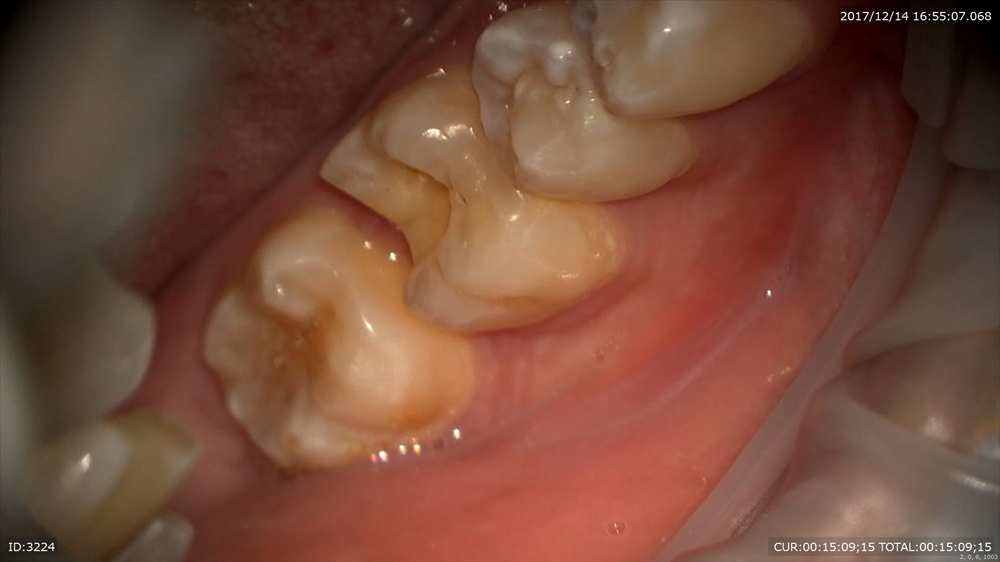

もう1つ虫歯のケース

歯が割れています。マイクロスコープで修復へ。

やはり自然な色が笑った時も美しいですね。